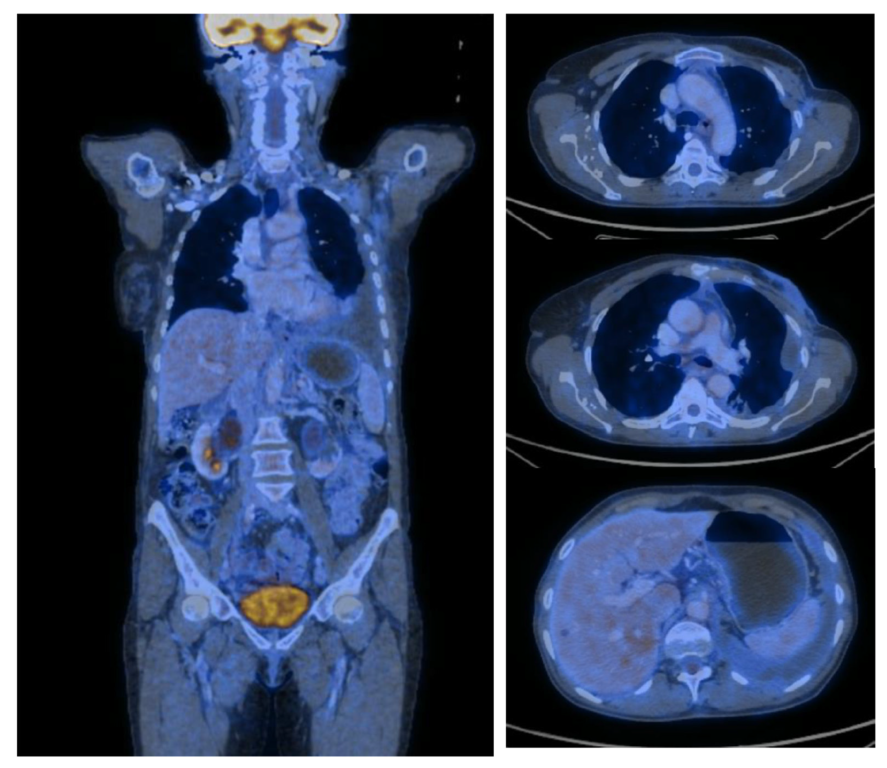

2. Case Report